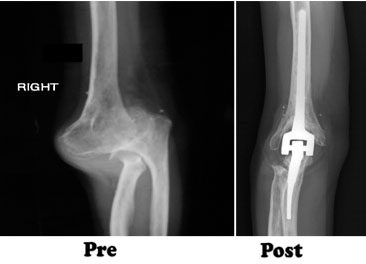

In total elbow replacement surgery, the damaged parts of the humerus and ulna are replaced with artificial components. The artificial elbow joint is made up of a metal and plastic hinge with two metal stems. The stems fit inside the hollow part of the bone called the canal.

To reach the elbow joint, your surgeon will make an incision (cut), usually at the back of the elbow. After making the incision, your surgeon will gently move muscles aside to get access to the bone. After removing scar tissue and spurs around the joint, your surgeon will prepare the humerus to fit the metallic piece that will replace that side of the joint. The same preparation is done for the ulna.The replacement stems are placed into the humerus and ulna bones, and kept in place with a bone cement. The two stems are connected by a hinge pin. After the wound is closed, a padded dressing is then placed to protect the incision while it heals. Some surgeons will place a temporary tube in the joint to drain the surgical fluid. This tube can be easily removed in your hospital room within the first few days after surgery.